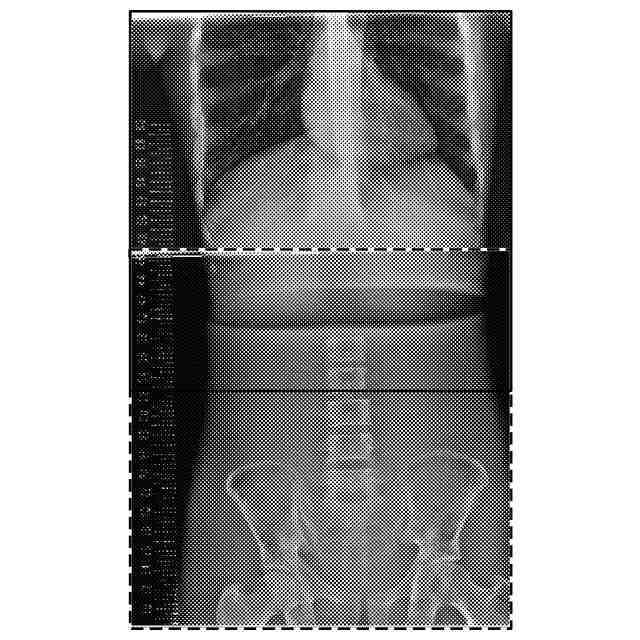

【解決手段】放射線画像処理装置として機能するコンソール30は、被写体に対し、それぞれ異なる撮影条件で撮影した複数の放射線画像を取得する画像取得部として機能する制御部31と、複数の放射線画像のうち少なくとも一の放射線画像の画素値を補正する画素値補正部、複数の放射線画像を合成して一の合成画像を取得する画像合成部として機能する画像処理部36と、を備え、複数の放射線画像の各々の放射線画像は、少なくとも一つ以上の他の放射線画像との画像重複領域を有し、画素値補正部は、少なくとも一の放射線画像の画素値の最大値が、画像の階調の最大値以下となるように画素値を補正する。

従来、放射線源の照射方向を体軸方向に変えることで得た複数の画像を合成させた合成画像を作成する方法(いわゆる首振り長尺)が知られている。

当該方法においては、放射線を複数回被写体に曝射する必要がある。そのため、被写体に健康上の悪影響が生じるおそれがある。そこで、例えば特許文献1及び2には、画像撮影の度に撮影条件を変更することで曝射の影響を抑えて、画像合成時に各画像の画素値を自動で補正する方法が記載されている。

しかしながら、特許文献1及び2には、画素値補正の具体的な方法については記載されていない。そのため、合成画像の画素値が階調の最大値以上となって(いわゆる濃度飽和)黒潰れを起こし、読影が困難になり得る。